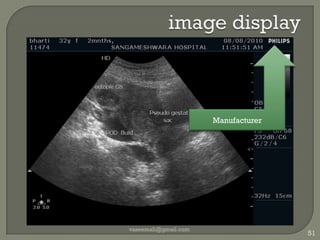

image displayvaseemali@gmail.com51Manufacturer